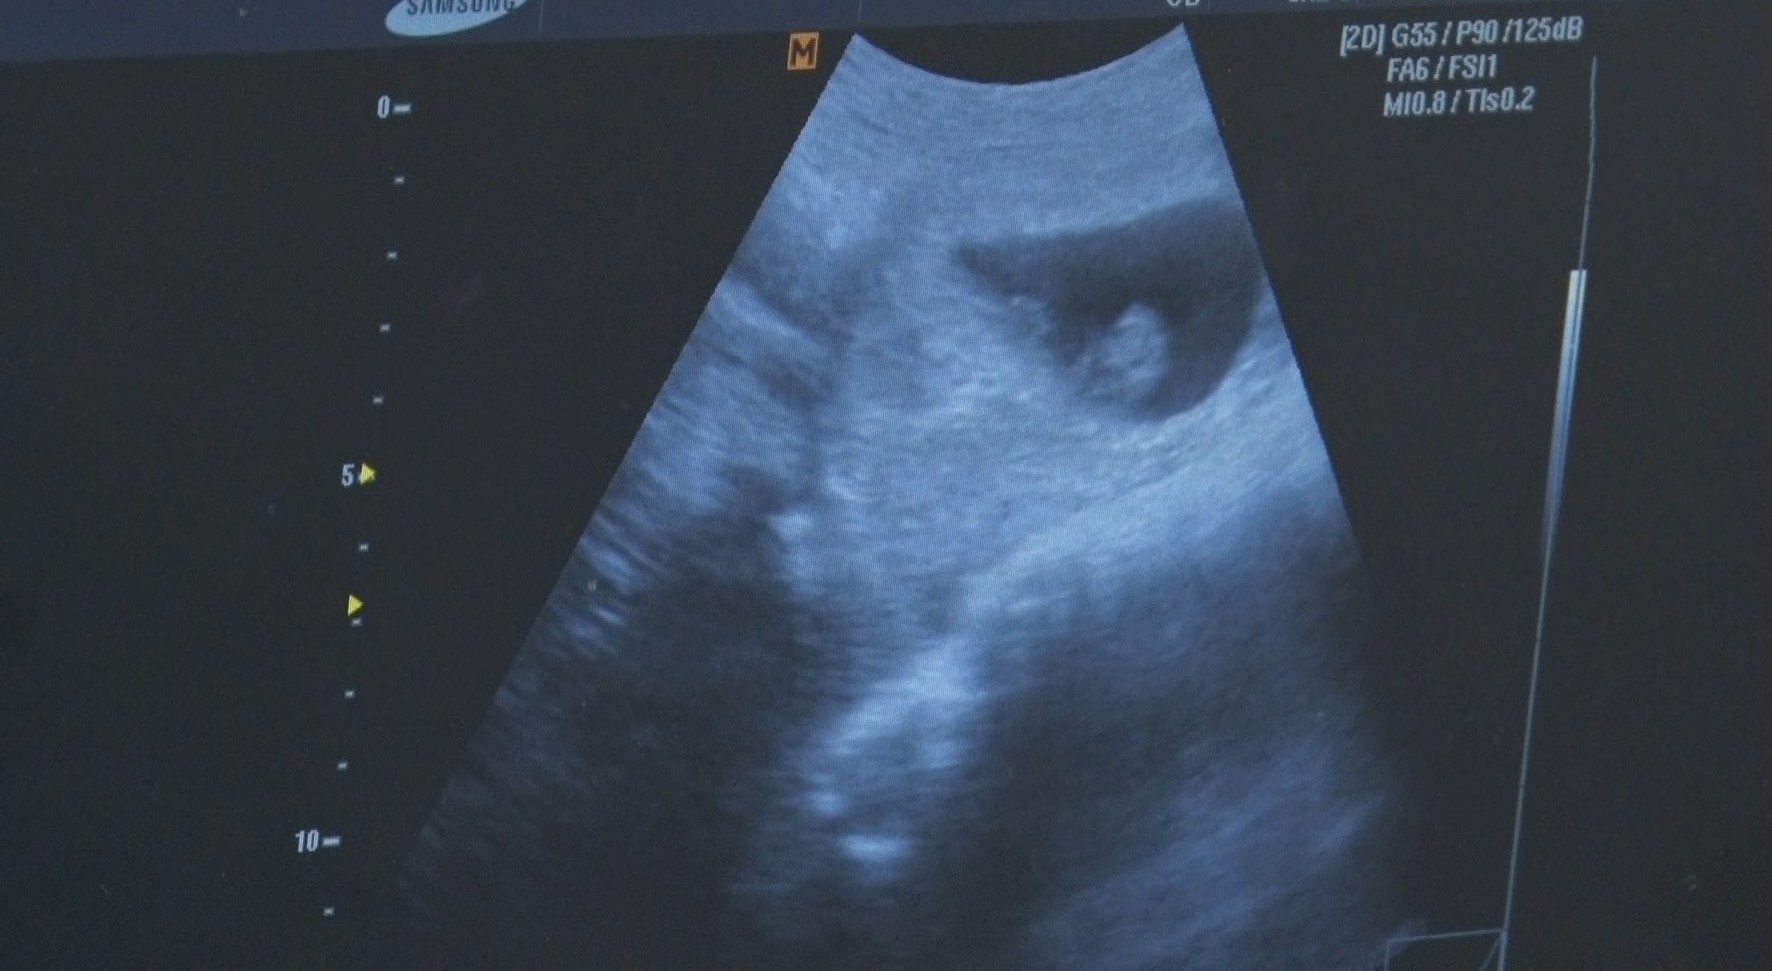

Grad Loznica otvorio je mogućnost prijave za postupak vantelesne oplodnje (VTO) uz podršku sredstava predviđenih javnim programom. Ovaj program je namenjen onima koji ne mogu da ostvare pravo na finansiranje…